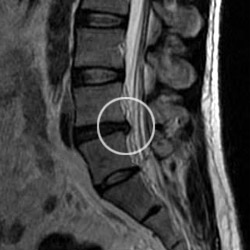

MRI image of the lumbar spine showing a disc herniation compressing the sciatic nerve

Figure 3: MRI scan showing a disc herniation in the lower spine, one of the most common causes of sciatica.